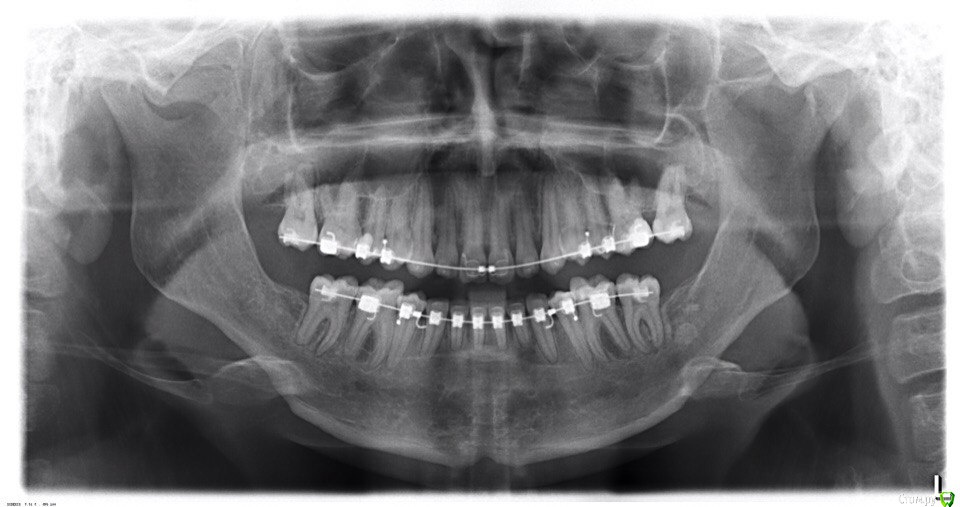

annurka Опубликовано 12 сентября, 2017 Поделиться Опубликовано 12 сентября, 2017 (изменено) здравствуйте! 24 года, дисфункция ВНЧС, дистальный прикус (1,4см), ортодонтическое лечение начато с ношения каппы для разгрузки сустава (привыкла подтягивать НЧ к верхней) в 2012 году. проведено лечение: удаление всех 8к (непрорезавшиеся), расширение ВЧ (аппарат дерихсвайлера), выравнивание зубных рядов, сепарация нижних резцов (резцы были наклонены), места не хватило - удаление 2 нижних 4к, выравнивание кривой шпее, двухчелюстная остеотомия; выравнивание окклюзионных контактов (резиновые тяги) проблема: между верхними и нижними резцами расстояние 5мм к трг (внизу фото) есть расшифровка.все идет к снятию брекетов, и с эстетической точки зрения меня все устраивает. но не до конца устраивает в функциональном плане (я не могу пропихнуть палец между зубными рядами, как раньше, но все также подтягиваю челюсть кпереди когда ем, говорю)стараюсь контролировать это, но даже улыбнуться не могу не подтянув - иначе у меня некрасиво вырисовывается подбородок, неправильно произношу звуки при разговоре.сразу после остеотомии состыковка резцов была ок - нижние зубы были за верхними, но мы с ортодонтом занялись состыковкой и других зубов (которые тогда не соприкасались), и когда добились контактов жующих сторон, разошлись резцы.UPD: и еще есть черные треугольники на НЧ - с ними тоже очень хочется разобраться лечащий ортодонт говорит, что это в целом норма, с учетом моего случая. и возможно это так, но я очень хочу послушать еще мнений, возможно стоит удалить 2 зуба наверху, чтобы верхняя челюсть подошла по размер нижней? [боюсь что простой сепарации может не хватить и как в случае с нижними резцами придется и сепарацию делать, и удалять зубы.] может быть еще есть другой способ добиться нормального прикуса, без "нюансов"?изначально я пошла на все это лечение, чтобы остановить разрушение сустава (однажды проснулась и не смогла рот даже открыть, еще до лечения), полагала, что брекеты и члх исправят если не ситуацию, то причину, но я все еще двигаю НЧ вперед к ВЧ. с остеотомии прошел почти год (поэтому на изменение картины эластиками я уже не надеюсь), брекеты ношу почти 4 года. заранее всем спасибо за отклик! Изменено 12 сентября, 2017 пользователем annurka 1 Ссылка на комментарий

annurka Опубликовано 13 сентября, 2017 Автор Поделиться Опубликовано 13 сентября, 2017 (изменено) А До лечения есть ТРГ посмотреть? И фото какие-нибудь?есть трг сверху - сразу после остеотомии, снизу - через полгода после (когда резцы отошли друг от друга на 5мм) до лечения вообще точно делал ортодонт (снимки, слепки, фото), если в клинике это сохранили, я смогу сфотографировать. далее фото в процессе лечения - 4ки нижние еще не удалены, один хирург был готов так оперировать, другой сказал, что наклон нижних резцов неправильный и нужно как и было запланировано удалить 4ки, сепарации недостаточно.челюсть расслаблена как есть: НЧ подвинута к ВЧ для наглядности: есть фото слепков того периода, но форум ругается на слишком большой размер. если нужно - уменьшу залью) Изменено 13 сентября, 2017 пользователем annurka 1 Ссылка на комментарий

annurka Опубликовано 13 сентября, 2017 Автор Поделиться Опубликовано 13 сентября, 2017 (изменено) вот трг до начала лечения, фото к сожалению нет, если только из жизни) расшифровка трг ДО (где выделено синей ручкой) и недавнее Конечно контакты не идеальны, но если удалить 4ки наверху нижняя треть лица будет иметь довольно вогнутый вид спасибо за комментарий! а если сделать сепарацию резцов, тогда получится избежать вогнутости профиля? С ДВНЧС у вас сейчас проблемы остались? Можно рассмотреть совместно с врачом аппараты для выдвижения нижней челюсти,если тяги не справляются не было до недавнего времени - сейчас иногда болит в области сустава слева (видимо потому что контакты справа уже есть, а слева в процессе, поэтому нагрузка на челюсть неравномерная ?). до операции (но после начала лечения брекетами) сустав не беспокоил, надеюсь это просто период реабилитации.насчет аппаратов по выдвижению НЧ - спасибо, передам ортодонту.с6нимки к сожалению выполнены в разных клиниках, но мне казалось что если судить по трг через полгода, то НЧ там же, где была закреплена титановыми пластинами сразу после остеотомии (но проблема с резцами тогда уже возникла)... или мне так только кажется и произошел рецидив? думаете ее можно еще двинуть вперед? Изменено 13 сентября, 2017 пользователем annurka Ссылка на комментарий

annurka Опубликовано 23 сентября, 2017 Автор Поделиться Опубликовано 23 сентября, 2017 (изменено) решила не трогать свои 4ки) подскажите кто-нибудь живой, сепарации верхних зубов будет достаточно?и если сепарировать, то только резцы (от клыка до клыка) или лучше весь ряд, или наоборот только боковой отдел? Изменено 23 сентября, 2017 пользователем annurka Ссылка на комментарий